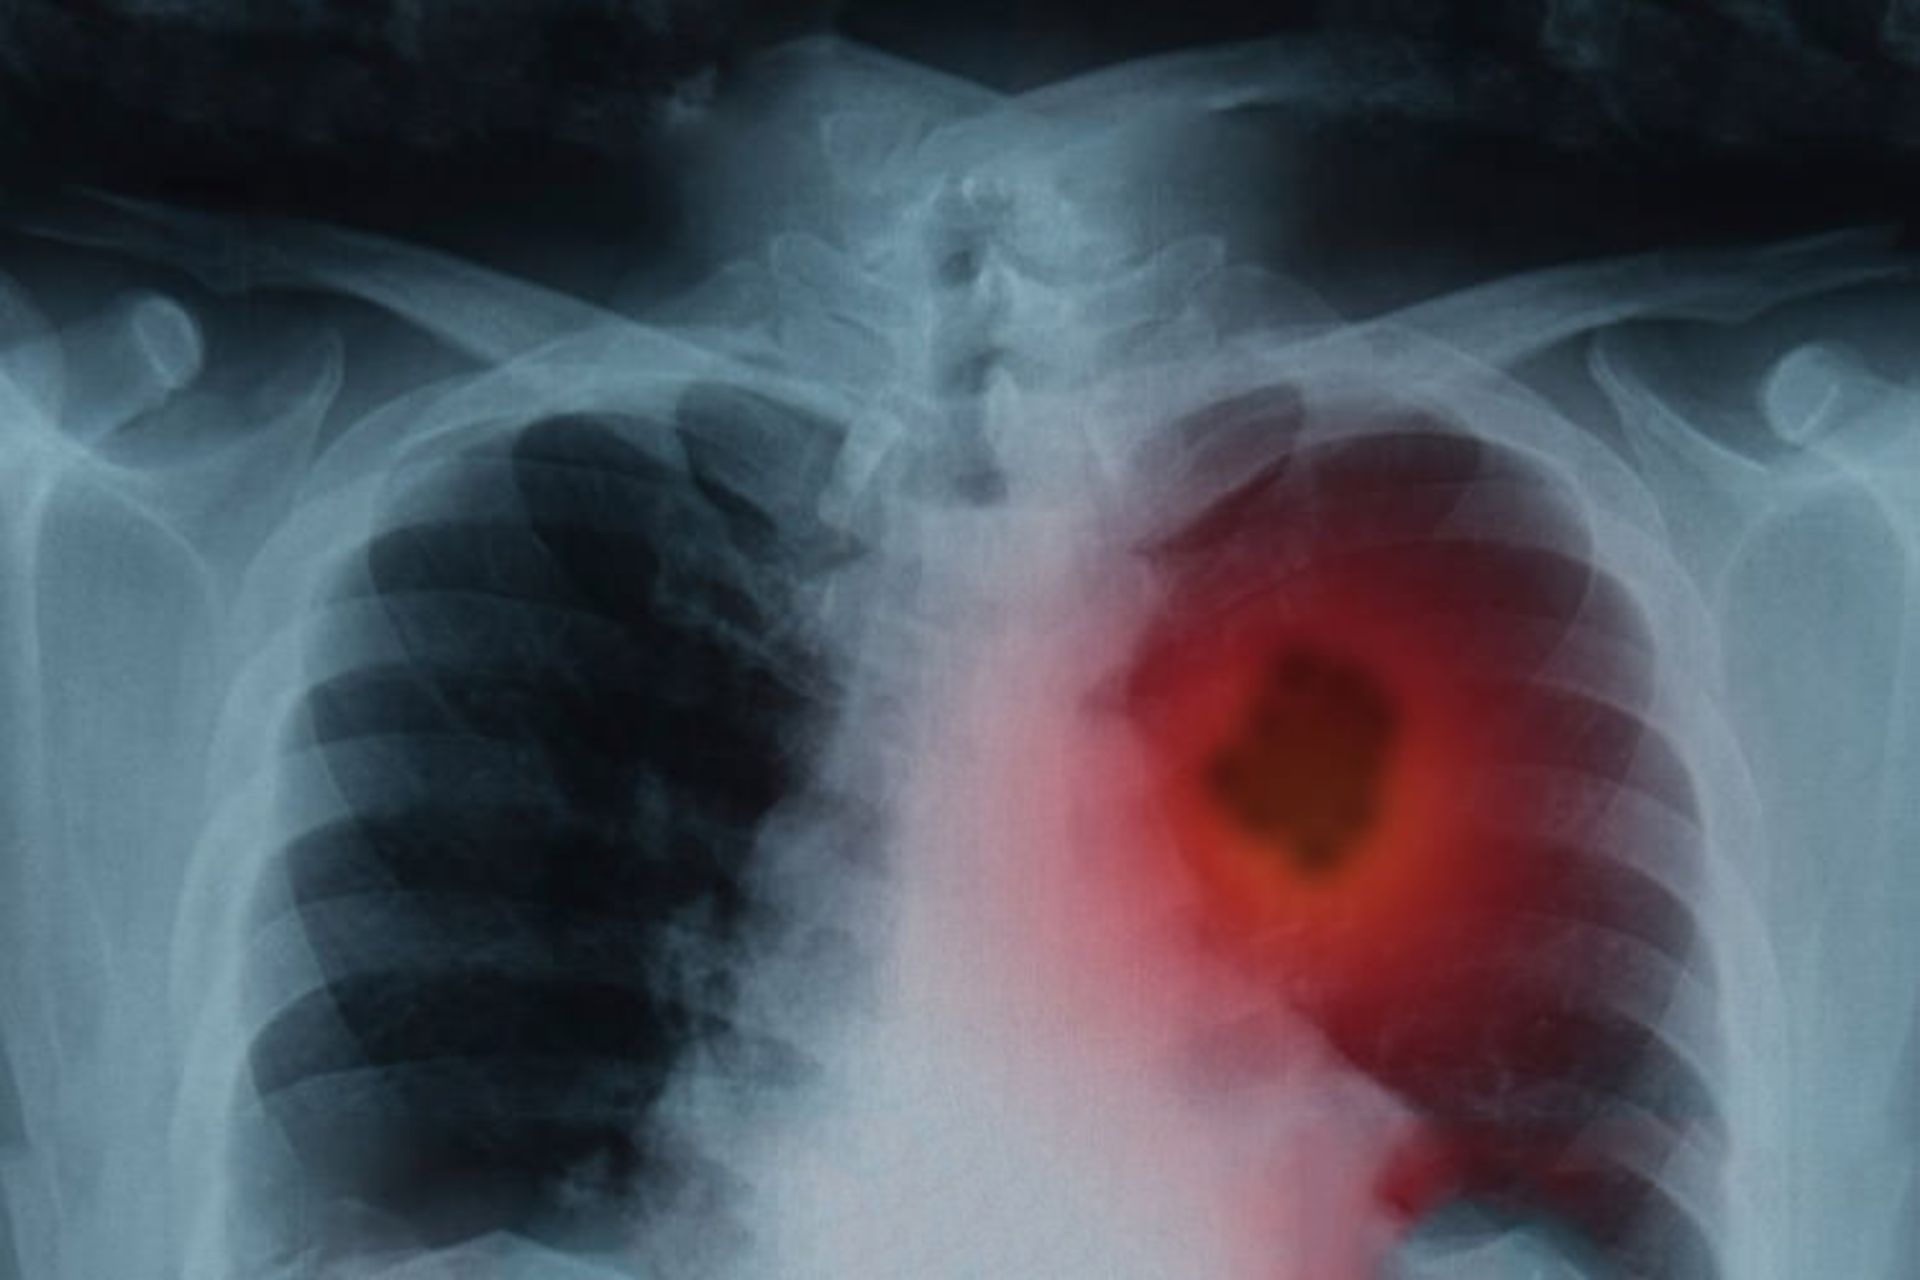

بر اساس یک مطالعه‌ی جدید، مصرف مکمل‌های B12 و B6 که قبلا تصور می‌شد در مقابل سرطان محافظت می‌کنند، رابطه‌ی مستقیمی با افزایش خطر سرطان به اندازه‌ی دو تا چهار لایه دارد. محققان در دانشگاه ایالتی اوهایو به این نتیجه رسیدند که این خطر در مردان به ویژه در افراد سیگاری افزایش یافته است.

پس از شش سال، محققان ابتلا به سرطان ریه را در شرکت‌کنندگان بررسی کردند. پس از کنترل بسیاری از فاکتورهای شناخته شده از خطر نفوذ سرطان، محققان افزایش ۳۰ درصدی در خطر سرطان ریه‌ی مرتبط با مصرف ویتامین B12 (جذب‌شده به صورت یک ویتامین مستقل) و افزایش ۴۰  درصدی خطر را برای مصرف‌کنندگان B6 گزارش کردند.

این اثر برای ویتامین‌های B در مولتی‌ویتامین‌ها یا در زنان مشاهده نشد. برای مردان که دُزهای بالایی از مکمل‌های مستقل را به مدت ده سال مصرف می‌کردند، خطر سرطان ریه دو برابر بود و هنوز هم در مردان سیگاری وجود دارد.

مقدار دز تأثیرگذار در افزایش خطر سرطان ریه در این مطالعه بیشتر از ۲۰ میلی‌گرم به ازای هر روز مصرف ویتامین B6 و بیشتر از ۵۵ میکروگرم به ازای هر روز مصرف ویتامین B12 است که به عنوان مکمل‌های مستقل مصرف می‌شوند.